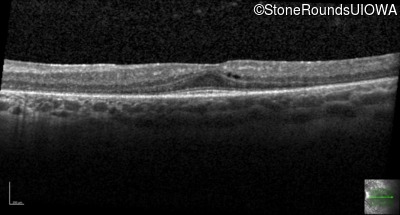

The parents of this 24 year old woman first noticed that she had poor peripheral vision when she was two years of age. She also had difficulty seeing in dim light.